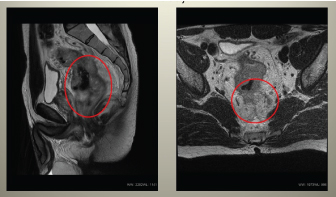

A 49-year-old male presented with abdominal pain and defecation problems. Colonoscopy examination showed ulcerating tumour 8 cm over the anal opening, histologically-tubular adenoma, CEA - 28.4 ng/ml, CA 19-9 - 31.6 U/ml. A week later local and systemic dissemination of process was radiologically diagnosed (Figures 1-3).

Figure 1. Pelvic MRI showing malignant tumour of rectum with pararectal spread, wide specific regional lymphadenopathy and mesorectal fascia infiltration.